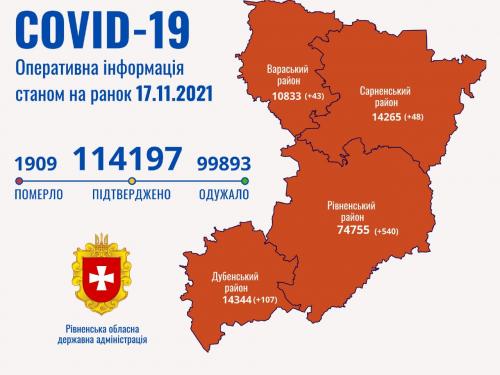

Пів тисячі - у важкому стані, 9 жителів Рівненщини померли за добу від коронавірусу